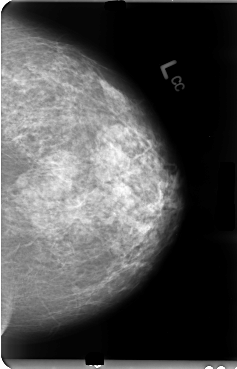

B_3036_1.LEFT_MLO

LEFT_MLO LINES 4760 PIXELS_PER_LINE 3120 BITS_PER_PIXEL 12 RESOLUTION 50 NON_OVERLAY